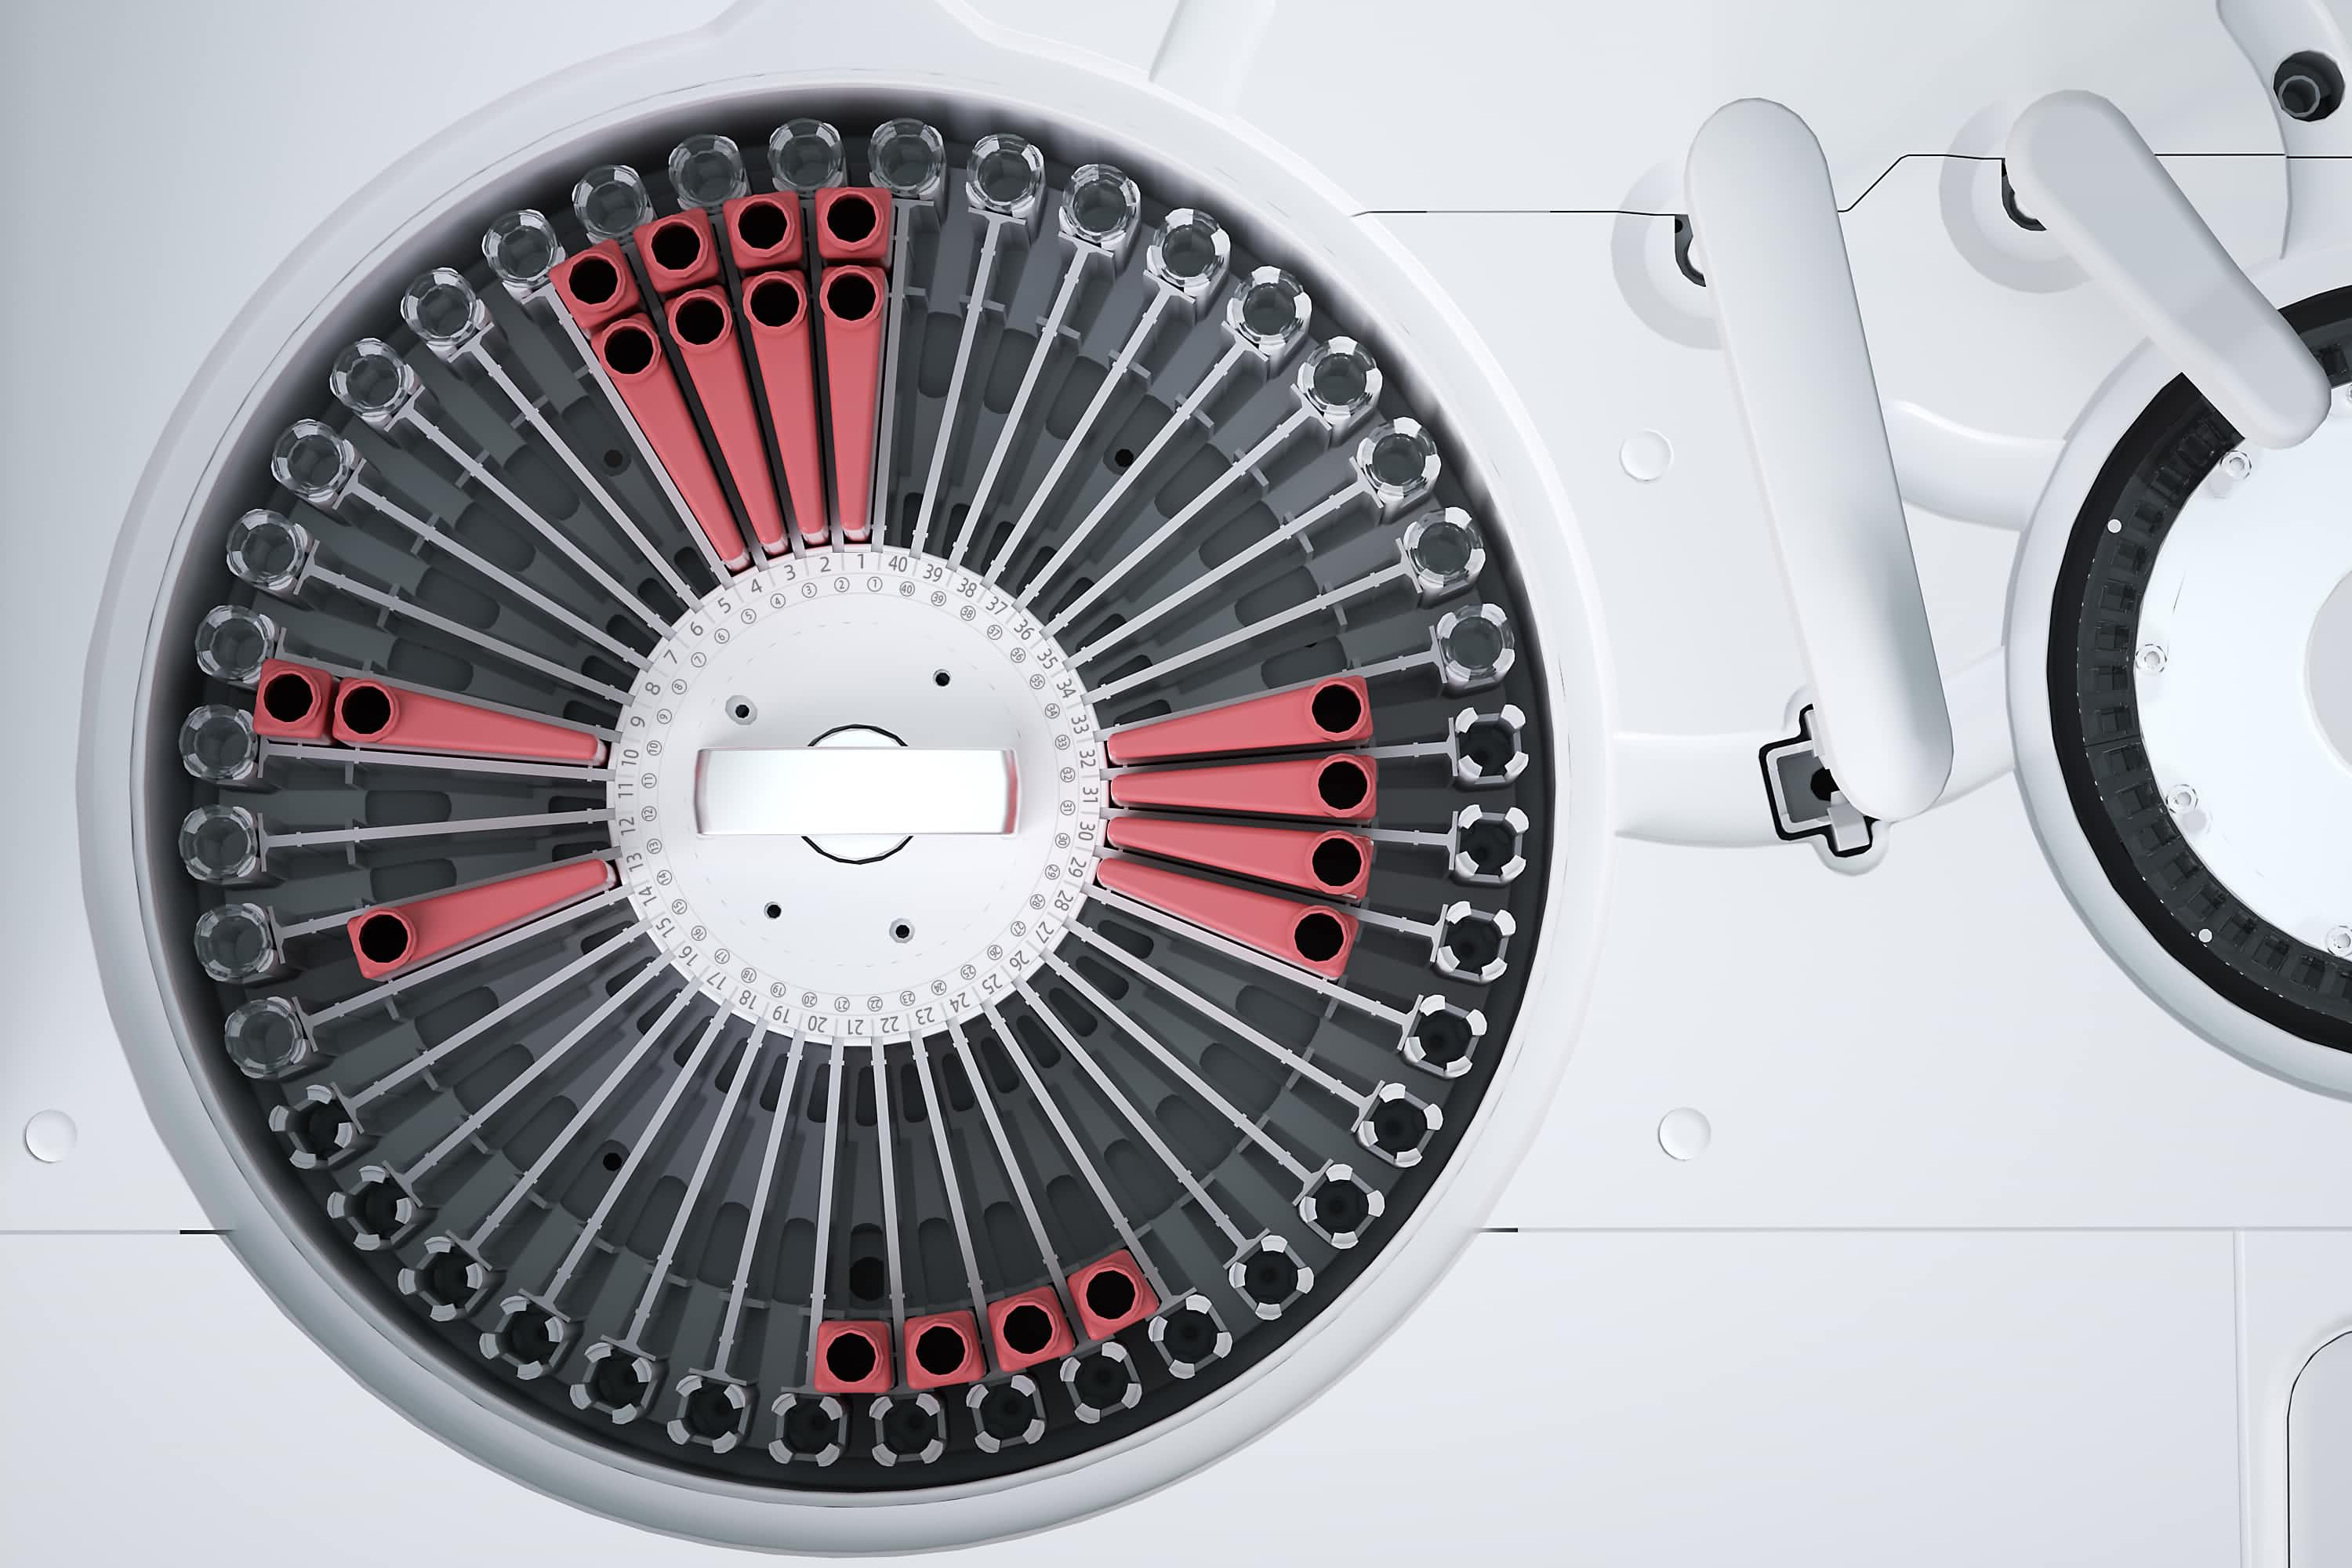

80个试剂位,40个样本位,试剂盘内置帕尔帖冷却系统。

40 个样本位

80 个试剂位,试剂盘 24 小时不间断冷藏